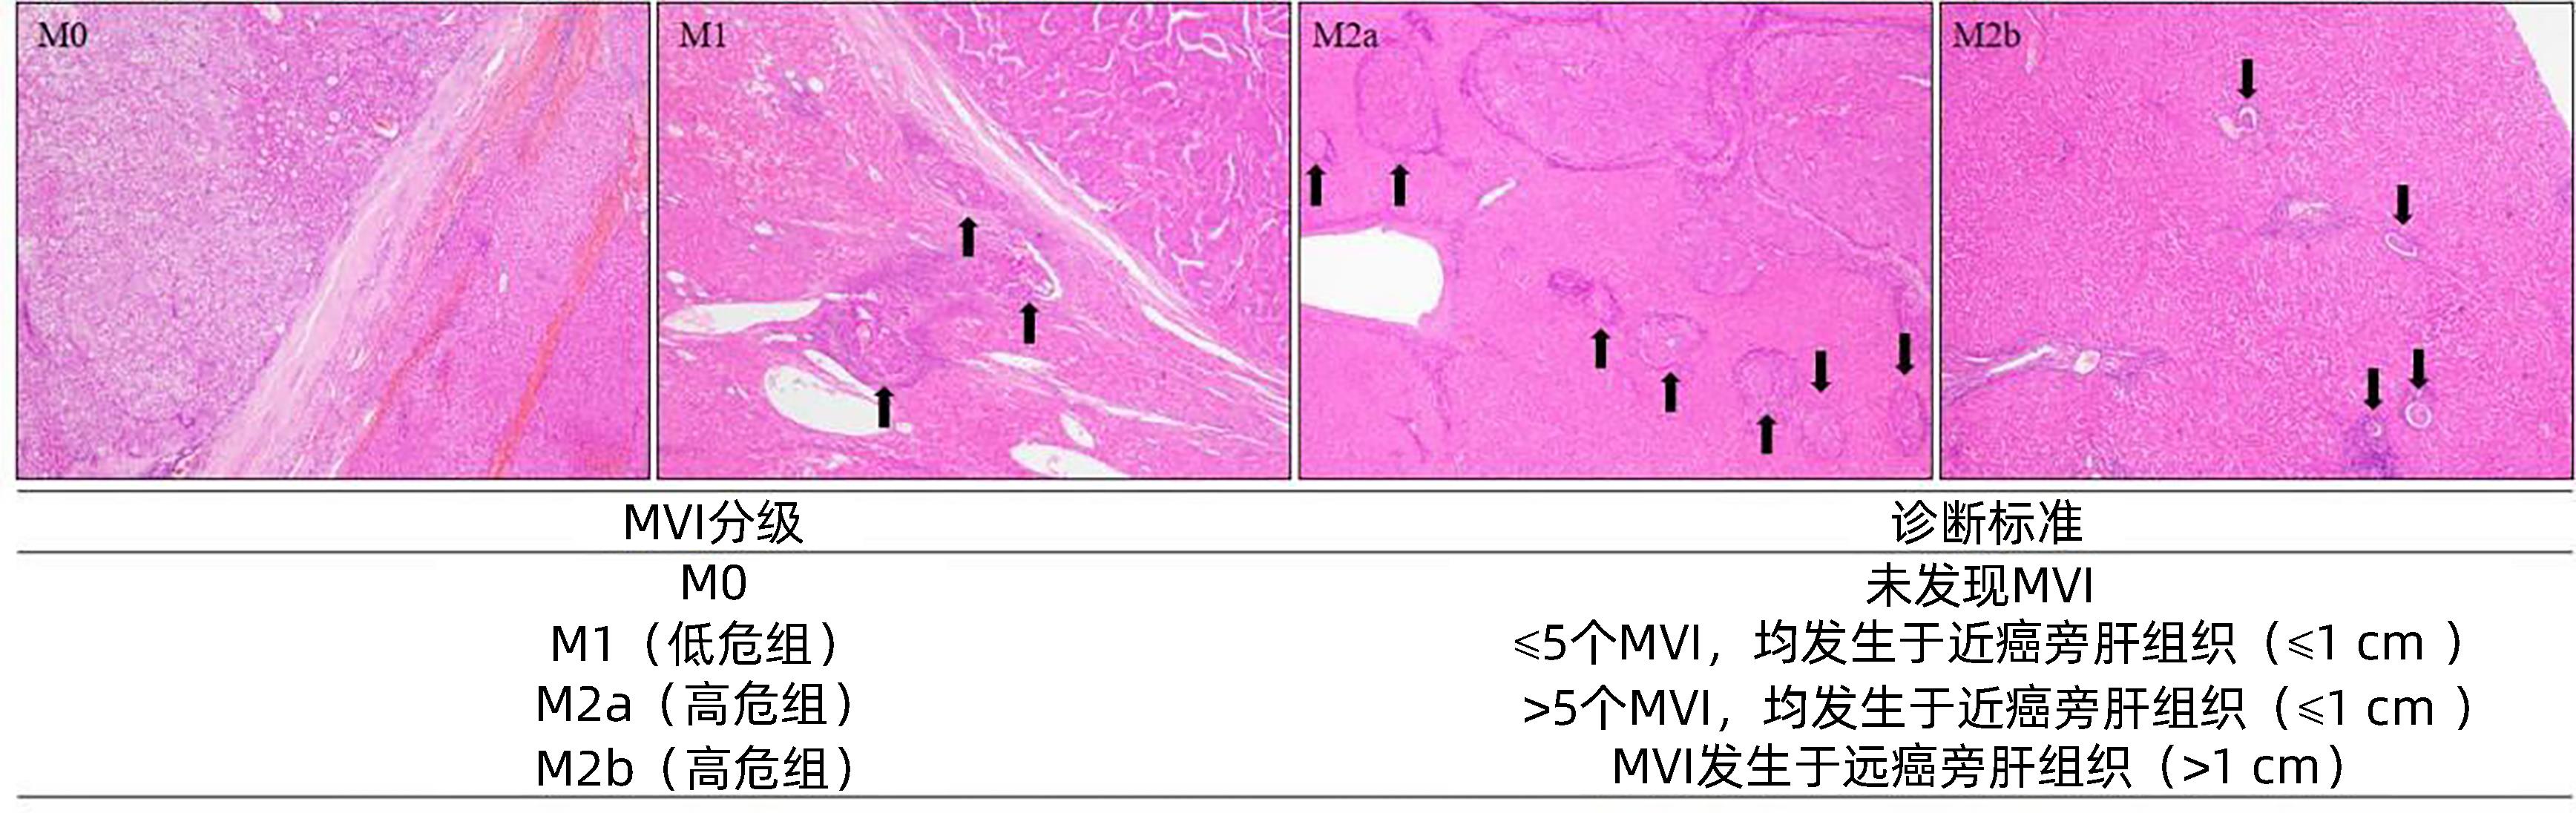

原发性肝癌诊疗指南(2024年版)

中华人民共和国国家卫生健康委员会

2024, 40(5): 893-918. DOI: 10.12449/JCH240508

摘要(14164) HTML (2012) PDF (1769KB)(3402)

摘要: